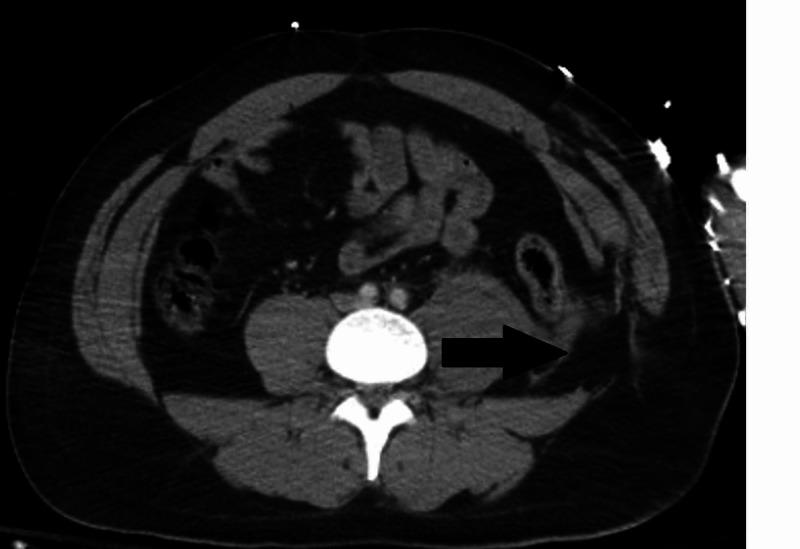

Iliac vein injury in the absence of pelvic fractures is rare. We present the case of a 27-year-old male involved in a motorcycle crash. Imaging demonstrated a lumbar hernia and pelvic hematoma in the absence of pelvic fractures. The patient became unstable and required emergency surgery demonstrating an iliac vein injury requiring ligation. Diagnosis and management of this rare injury is reviewed.

在没有骨盆骨折的情况下,髂静脉损伤很少见。我们报告一例27岁男性摩托车事故病例。影像学检查显示存在腰疝和骨盆血肿,但无骨盆骨折。患者病情不稳定,需要紧急手术,术中发现髂静脉损伤并进行了结扎。本文对这种罕见损伤的诊断和处理进行了综述。